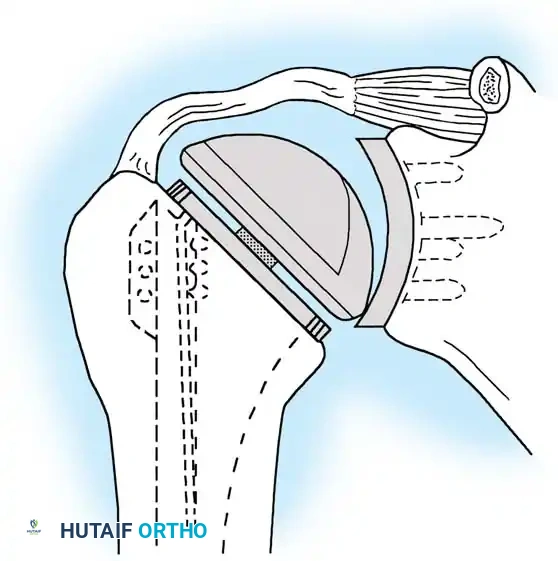

Reverse Total Shoulder Arthroplasty (rTSA)

The rTSA fundamentally alters shoulder biomechanics. By medializing and distalizing the center of rotation, it increases the deltoid moment arm and recruits more anterior and posterior deltoid fibers for elevation, bypassing the need for a functional rotator cuff.

Surgical Nuances for rTSA:

* Glenoid Baseplate: Must be positioned inferiorly on the glenoid to avoid scapular notching. A slight inferior tilt (10 degrees) is often utilized.

* Glenosphere: Typically 36 mm or 42 mm. Larger spheres increase stability and range of motion but may increase the risk of notching.

* Humeral Stem: Often placed in 0 to 20 degrees of retroversion.

Clinical Pearl: Tensioning is the most critical step in rTSA. The joint should be stable in all planes. If the joint dislocates easily, a thicker polyethylene insert or a larger glenosphere is required. However, over-tensioning can lead to acromial stress fractures or brachial plexopathy.